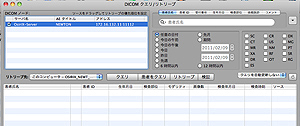

OsiriX(オザイリクス)は、医用画像ビューワの表示とその画像からの分析す

るために開発された高性能なDICOMビューワです。また同時に DICOM通信

機能も備えた簡易的PACS としても利用可能な Mac OSX 専用アプリケー

ションです。無料でだれでもダウンロードできます。